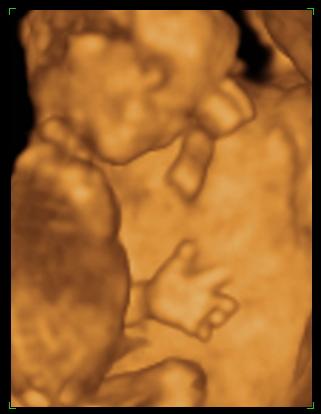

Tök sokára jutottam be, mert ugye nem volt időpontom. Meg ultrahangozott a doki, hát érdekes volt. Először nem mondott semmit, csak a végén közölte, hogy ok, most menjek el sétálni, negyed órára és majd visszahívnak, mert nem jól fekszik a baba

én még ilyen nehézkes nyaki redő mérést nem pipáltam... ok lementem gyalog a lépcsőn, ittam egy kávét, majd fel gyalog a negyedikig. Na ez meg is tette hatását- mikor visszahívtak, elkezdte mérni, megmérte vagy tízszer (!!!) a nyaki redőt. Nem mondott semmit. De én láttam alul a sarokban, hogy oda volt írva az NT, és hogy folyton ilyeneket mért, hogy 2,1,2,2,2,3....stb. mindig ekörül. Már törölgette a homlokát, összenéztek az asszisztenssel... kezdtem nagyon unni. Mondja egy idő után, hogy hát ő nem érti, de neki meg sem közelíti a 3-at.... mondja max 2.3-at mért idáig. Na mondom, az jobban hangzik, mint a 3.3. Akkor utána elkezdett a gyerek pörögni, kiegyenesedett, akkor is ilyeneket méregetett, majd a lepénytapadásra semmit nem mondott

, és mikor a gyerek kicsit hátrahajtotta a fejét, na akkor mért 2,8-3-at. És utána mondta, hogy ne haragudjak, de akkor ezt írja be, mert ha kicsit hátrahajtja a fejét, akkor vastagabb. De, szerinte nincs az 3 se, mindenesetre menjek el genetikai tanácsadásra....

Szoval tudjátok mit nem értek??? Nem az a normál állapot, ha nincs a feje hátrahajtva? Mikor pl. magasságot mérnek, akkor sem érvényes, ha hátrahajtom a fejemet,nem? Sőt ha a fejemet hátrahajtom, az én nyakam is vastagabb lesz, és megrövidül nem? Szerintetek másnak a nyaki redőjét is úgy mérik, hogy megvárják, míg hátrahajtja a fejét?!?!? Nem értem az egészet, komolyan... mindegy, a lényeg, hogy még így is kevesebbet mértek. szoval holnap megyek 11:30-ra a Bolgárkerékre a 4d uh-ra és a kombinált tesztre utána.